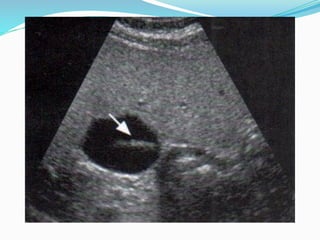

SOMBRA ACÚSTICA POSTERIOR

Ausencia de ecos por detrás de estructuras que son fuertes

reflectores o absorbentes del ultrasonido. Aparece como una

banda anecoica, oscura, posterior a un eco de alta amplitud

(proveniente de un reflector fuerte como el calcio, el aire o el

hueso). Útil para el diagnóstico de cálculos y quistes (sombras de

borde). Problemático en la ecografía abdominal (sombras del gas

intestinal y las costillas). Son producidas no sólo por los

reflectores fuertes sino también por el tejido conectivo que es

golpeado tangencialmente por el haz (ligamento redondo, tejido

conectivo en hilio hepático).

Los cálculos pequeños pueden producir una sombra acústica

sólo si están directamente dentro de la zona focal del

transductor.